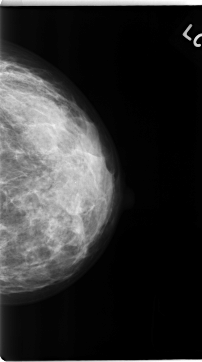

C_0139_1.LEFT_CC

LEFT_CC LINES 4704 PIXELS_PER_LINE 2624 BITS_PER_PIXEL 12 RESOLUTION 50 NON_OVERLAY